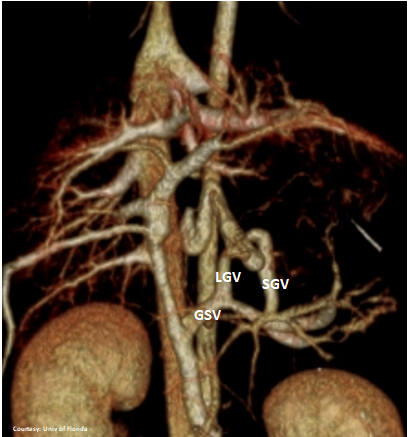

Does LEFT GASTRIC VEIN (LGV) enter the GASTROSPLENIC VEIN (GSV)?

Does the SHORT GASTRIC VEIN (SGV) contribute blood to the shunt?

“aLGC +SGV”